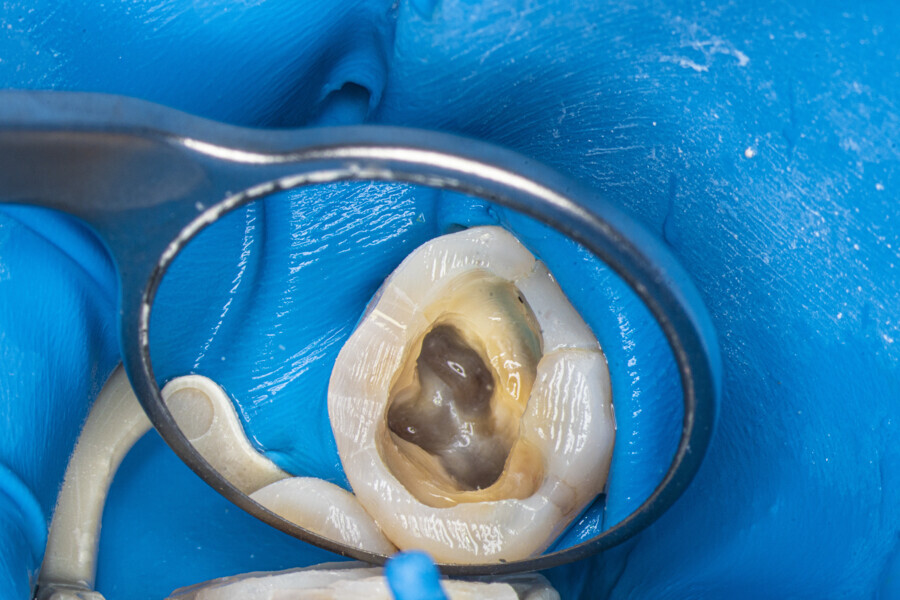

The first trials of the LPE concept were performed on extracted human molars. Although the dynamics of fluid during root canal irrigation are completely different in vivo than in extracted teeth, these kinds of trials provide initial information about the procedure. Some of these teeth had apices closed with a coat of wax and composite resin to close the apical delta and simulate the periapical tissue. After creation of the access cavity, the pulp chamber was cleaned with continuous irrigation with 5.25% NaClO activated with a SkyPulse laser (Fotona) in AutoSWEEPS mode (20 Hz, 15 mJ). A 25/0.07 reciprocating file (Shenzhen Perfect Medical Instruments) was used to perform the pre-flaring procedure. After opening the coronal third, continuous irrigation with 5.25% NaClO activated with the laser was used to clear the debris for 30 seconds. After removing the debris, a #10 C-PILOT file (VDW) was used to establish apical patency, without forcing the file if possible. In some cases, apical patency was reached already at this stage of root canal preparation. In all cases, the second step of instrumentation was the preparation of the middle third with the same file, and the same irrigation procedure was performed. Subsequently, the C-PILOT file was used to reach the apical foramen. At this stage, apical patency was reached in most cases, but in some roots, there was no possibility of entering the apical foramen. The working length was confirmed with a radiograph with the hand file. Usually, the next procedure to be done is apical preparation, but the LPE concept is based on an enhanced irrigation protocol. Following this protocol, irrigation was performed for 5 minutes with continuous flow of 5.25% NaClO activated with the SkyPulse laser in AutoSWEEPS mode (20 Hz, 20 mJ) with a conical sapphire fibre. The next step was alternating irrigation with 17% EDTA for 30 seconds, with 5.25% NaClO for 30 seconds and with 17% EDTA for 30 seconds, all activated with AutoSWEEPS, followed by irrigation for another 5 minutes with 5.25% NaClO activated with AutoSWEEPS. In most cases, the next step after this stage of enhanced irrigation was the calibration of the apical constriction rather than apical preparation per se, but this step requires further investigation.

Case 4 (Figs. 47–60)

A 35-year-old female patient was referred to the office owing to the lack of patency in the pulp chamber. The periapical radiograph and CBCT image confirmed that the pulp chamber was completely calcified. The calcification of the pulp chamber was removed with diamond-coated ultrasonic tips. After removing the calcification, four orifices were located and shaped in the sequence described previously. The LPE enhanced irrigation protocol with the SkyPulse laser was performed. In this case, the MB2 canal joined the MB1 canal approximately 4 mm before the apex and was shaped only to this length. Apical preparation and irrigation were performed as described previously. The periapical radiograph revealed that the MB2 canal had a separate apical part, which was cleaned with the irrigants and filled with the sealer, and that the palatal canal had two portals of exit.